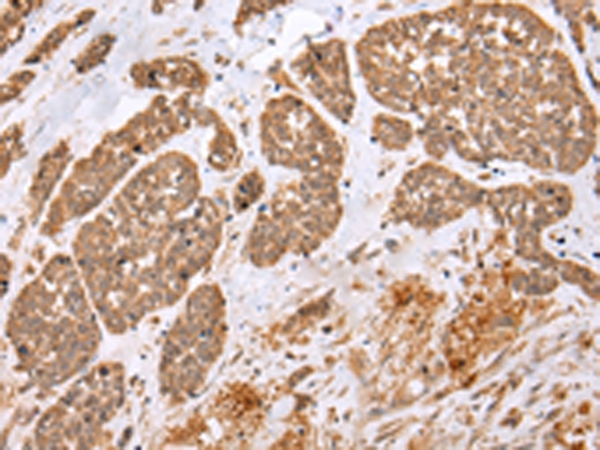

分类: 科研抗体货号: P43467别名: OF; XDP; BA2R; CCG1; CCGS; DYT3; KAT4; P250; NSCL2; TAF2A; N-TAF1; TAFII250; DYT3/TAF1; TAFII-250; TAF(II)250应用: WB,IHC反应种属: Human,Mouse